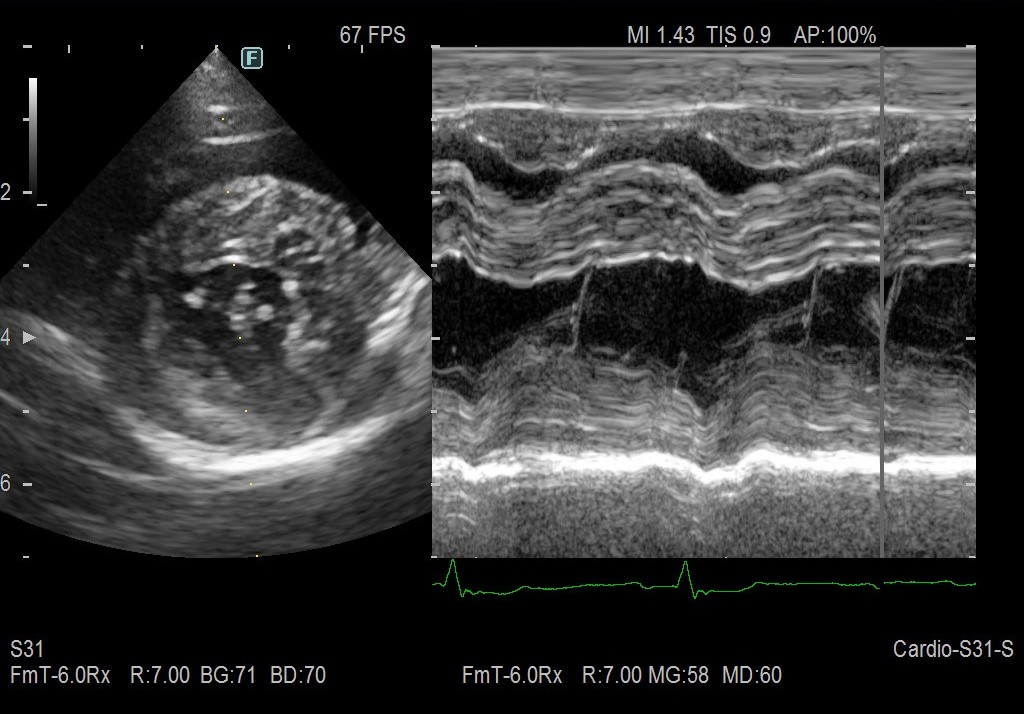

本稿トップのエコー画像は、下の円形部分が左心室で、その上の黒い部分が右心室内腔です。右心室が肺に血液を送り出す部分ですから、ホースの基部だと考えるとわかりやすいかと思います。

風船(肺)に血液を送りこめないので、ホースの基部(右心室)がパンパンに拡張して左心室を圧排しています。

左が治療前、右が治療後の画像です。